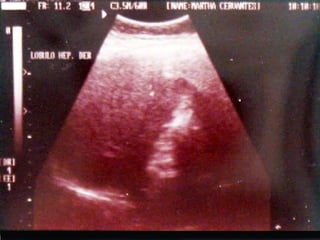

SONOGRAMA ABDOMINAL EVALUACIÓN TAMAÑO ( Hepatitis, I.C.C., Cirosis) FORMA (lobular en cirrosis) LOCALIZACIÓN ( de masas) PATRON SONOGRÁFICO ( hiperecoico gris)

SONOGRAMA ABDOMINAL EVALUACIÓN HIGADO SISTEMA BILIAR BAZO  RIÑONES PANCREAS ( no específico)

SONOGRAMA ABDOMINAL EVALUACIÓN  CAUSAS DE AUMENTO DIFUSO ECOS . Variante de la normalidad Falla cardiaca Hígado graso  Hiperalimención Cirrosis Malnutrición Infiltración maligna externa  Terapia con  corticoesteroides Mononucleosis infecciosa Enf. De Wilson Hepatitis severa

SONOGRAMA ABDOMINAL EVALUACIÓN CAUSAS DE AUMENTO FOCAL DE ECOS . Nódulos de regeneración Metástasis Tumores primarios Adenoma Hiperplasia nodular focal Infiltración grasa focal  Absceso Infarto Hematoma / Laceración Hepatitis (CMV)